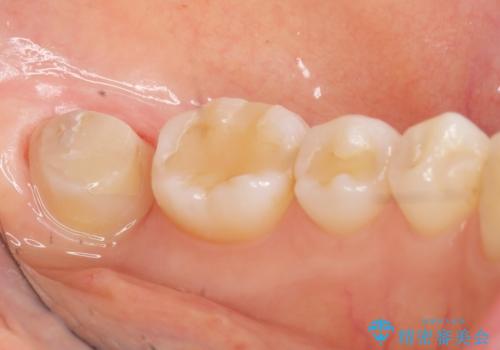

割れている奥歯を抜去後左上の機能していない親知らずを移植し、生着したのち根管治療・補綴を行いました。

インプラントや義歯を用いることなく咬合を回復することができ、喜んで頂けました。

治療期間も抜歯後3ヶ月以内かつ少ない来院回数(初診含めて6回)で治療を終えることができ、ご満足頂けました。

被せ物の種類:メタルボンドクラウン エコノミー フルベイク